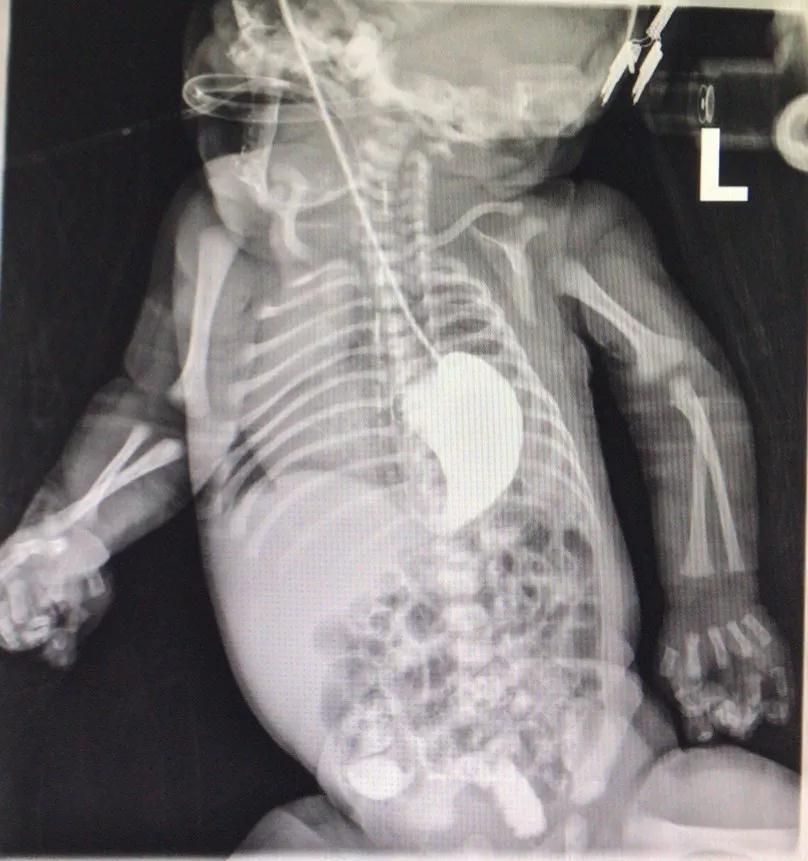

12月8日凌晨,天天出生。出生后,他很快就出现呼吸困难、发绀的情况。马上气管插管。检查显示,天天大部分的胃、结肠、脾脏都已经跑到胸腔里,左侧肺有一半以上已经被挤压得看不到了。